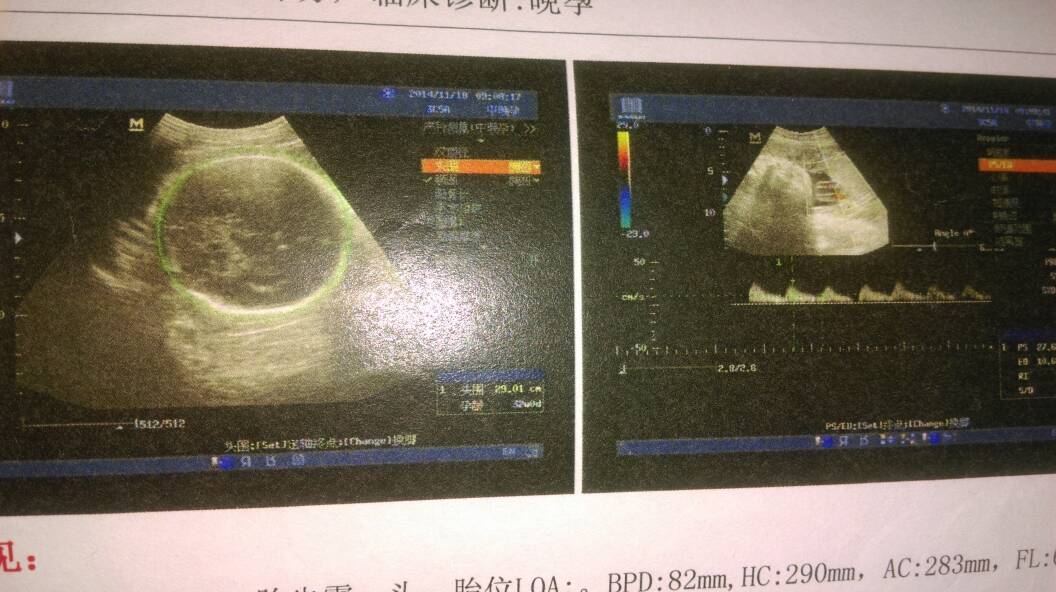

有没有宝妈会看b超单的,能帮我看看是男孩女孩吗 有没有宝妈会看b超单的,能帮我看看是男孩女孩吗 点击展开 轉身 ,陌路 2014-12-05 13:41 为您推荐: 其他回答 您好!根据图片是不能判断宝宝性别的,只能通过B超动态观察胎儿,不管男孩女孩宝宝健康就好。 cn#BBLQpuQVuf 2014-12-09 18:49 祝宝妈好运 幸福妈妈咪呀 2014-12-05 16:39 这个根本看不出男女的 多多的成长 2014-12-05 15:54 拉金币,祝宝宝健康快乐 呆萌朵朵和饼干小弟 2014-12-05 14:59 男女都一样的 杨静 2014-12-05 14:11 加载更多 相关问题 有没有会看男孩女孩的宝妈,帮我看看,我25周加3天了,90年的,5月6日最后的月经 我怀孕三个半月了,这是昨天做的B超单,帮我看看是男孩女孩吧!超声所见…胎心率:153次/分;胎盘:后…